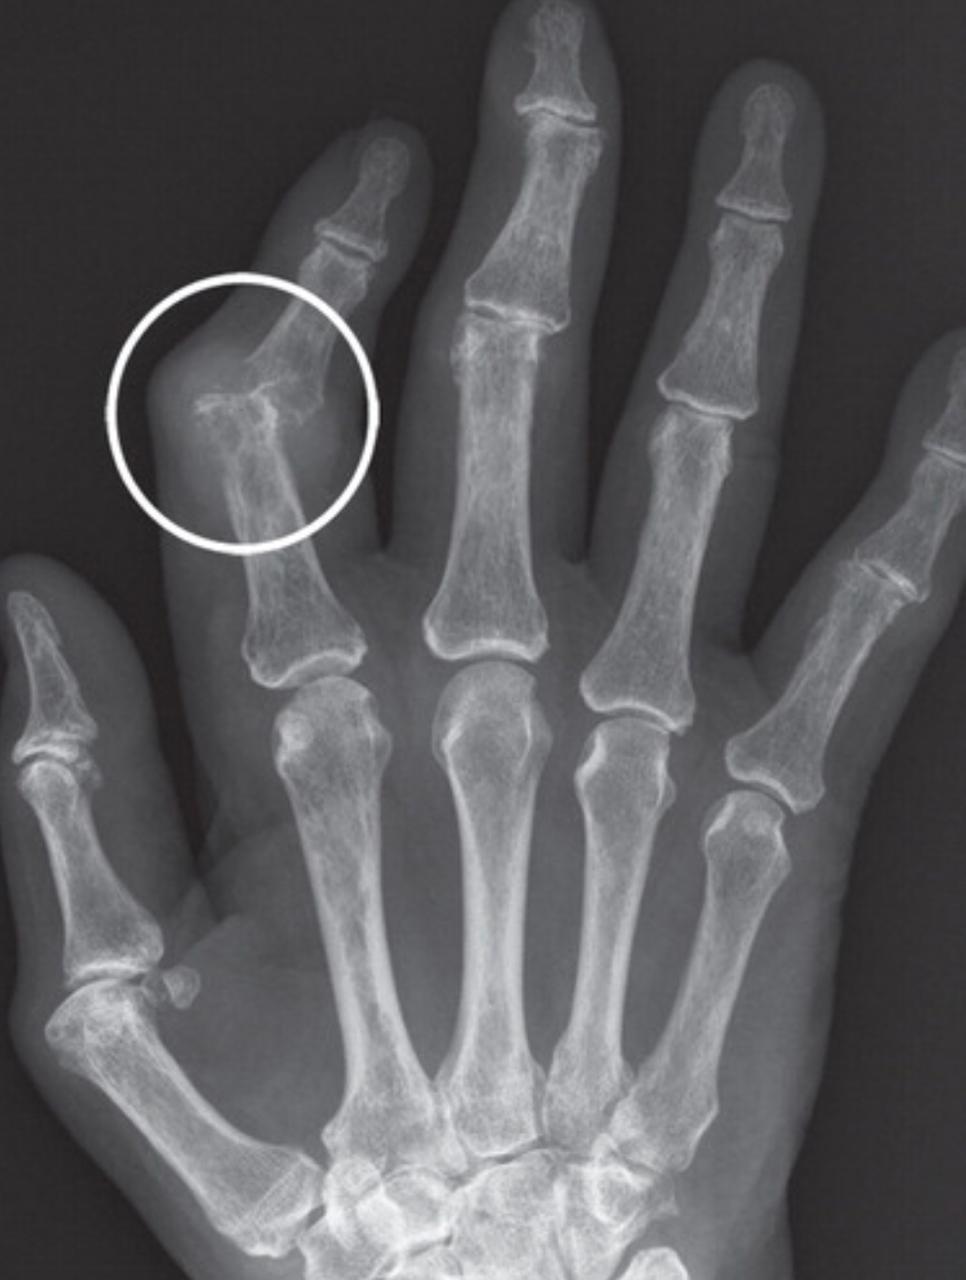

A Tillaux fracture is a traumatic Salter–Harris type III fracture through the anterolateral aspect of the distal tibial epiphysis, with variable amounts of displacement.

It accounts for 3-5% of pediatric ankle fractures and more commonly seen in girls. Tillaux feacture is seen in children nearing skeletal maturity (12-14 years old), when the medial epiphysis had closed but before the lateral side has done so.

The fracture commonly results from an abduction-external rotation force, causing the anterior tibiofibular ligament to avulse the anterolateral corner of the distal tibial epiphysis, at the opposite end to a Wagstaffe-Le Fort avulsion fracture, resulting in a Salter Harris Type III fracture.

Variability in fracture pattern is due to progression of physeal closure as anterolateral part of distal tibial physis is the last to close. When the lateral physis is the only portion not fused, external rotation may lead to Tillaux or Triplane fractures. Lack of coronal plane fracture in the posterior distal tibial metaphysis distinguishes this fracture from a triplane fracture.